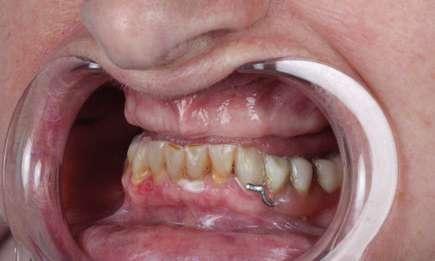

En su motivo de consulta demanda una “solución fija y menos voluminosa“ para rehabilitar su boca. (Fig. 1 y 2).

Los dientes inferiores remanentes a pesar de presentar lesiones cervicales y reconstrucciones previas presentan un buen estado periodontal y un pronóstico favorable.

Se propuso un plan de tratamiento consistente en la colocación de seis implantes y una prótesis fija implantosoportada en el maxilar superior, así como un cambio de los dientes de acrílico de la prótesis inferior y restauraciones de resina inyectada en los dientes anteroinferiores para restablecer los parámetros de dimensión vertical y orientación de planos oclusales.